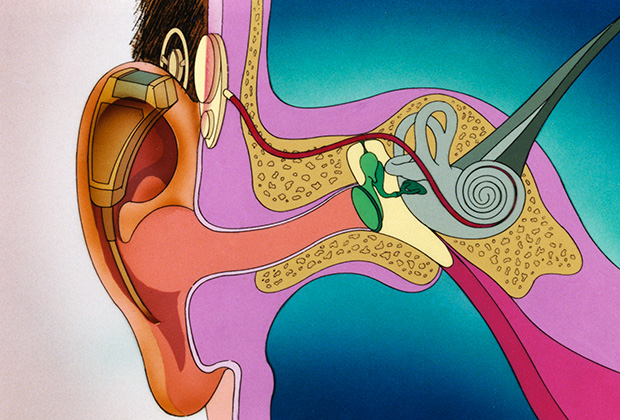

Современные слуховые аппараты при сенсоневральной тугоухости